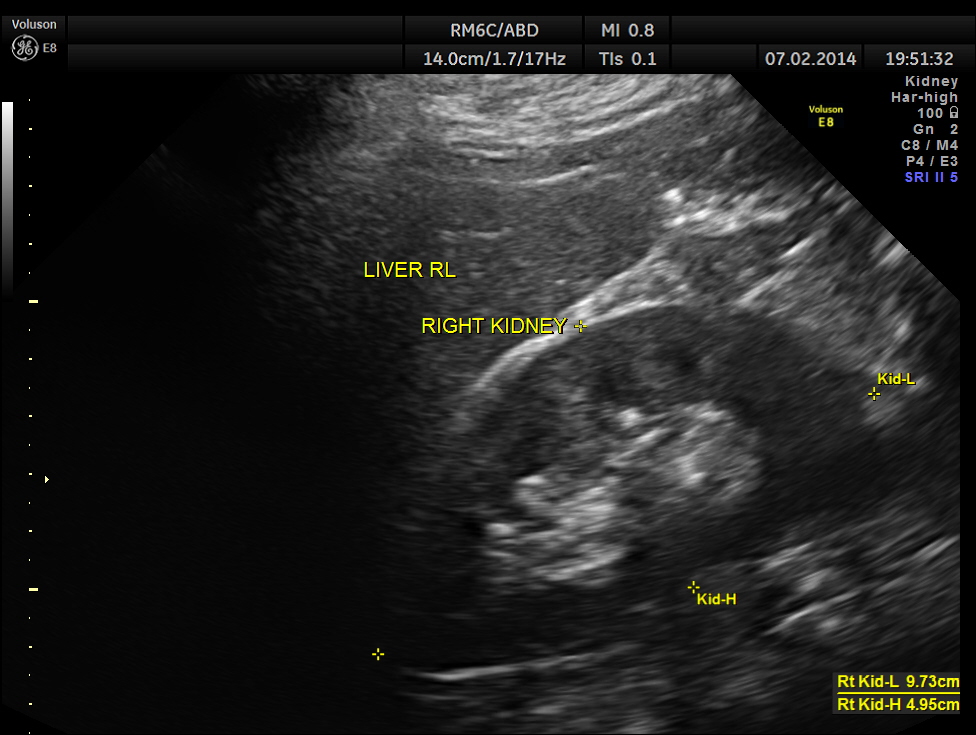

The following pictures show the testicles.Mild left hydrocele is also seen.

The kidneys appeared normal.